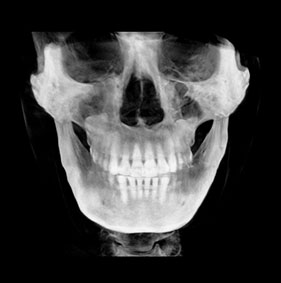

3D CT분석을 통한

정확한 코 재수술

원인 분석

코 재수술은 문제의 원인을

정확한 파악하는 것이 중요합니다.

V브이성형외과의

코성형 전담 의료진은

환자와 면밀한 상담을 통해서

현재 불만족의 원인을 파악하고

개선을 위한 방법을 모색합니다.

3D CT 분석을 통해서 해부학적인 상태를 확인하고,

기존 코수술로 인한 문제를 파악할 수 있습니다.